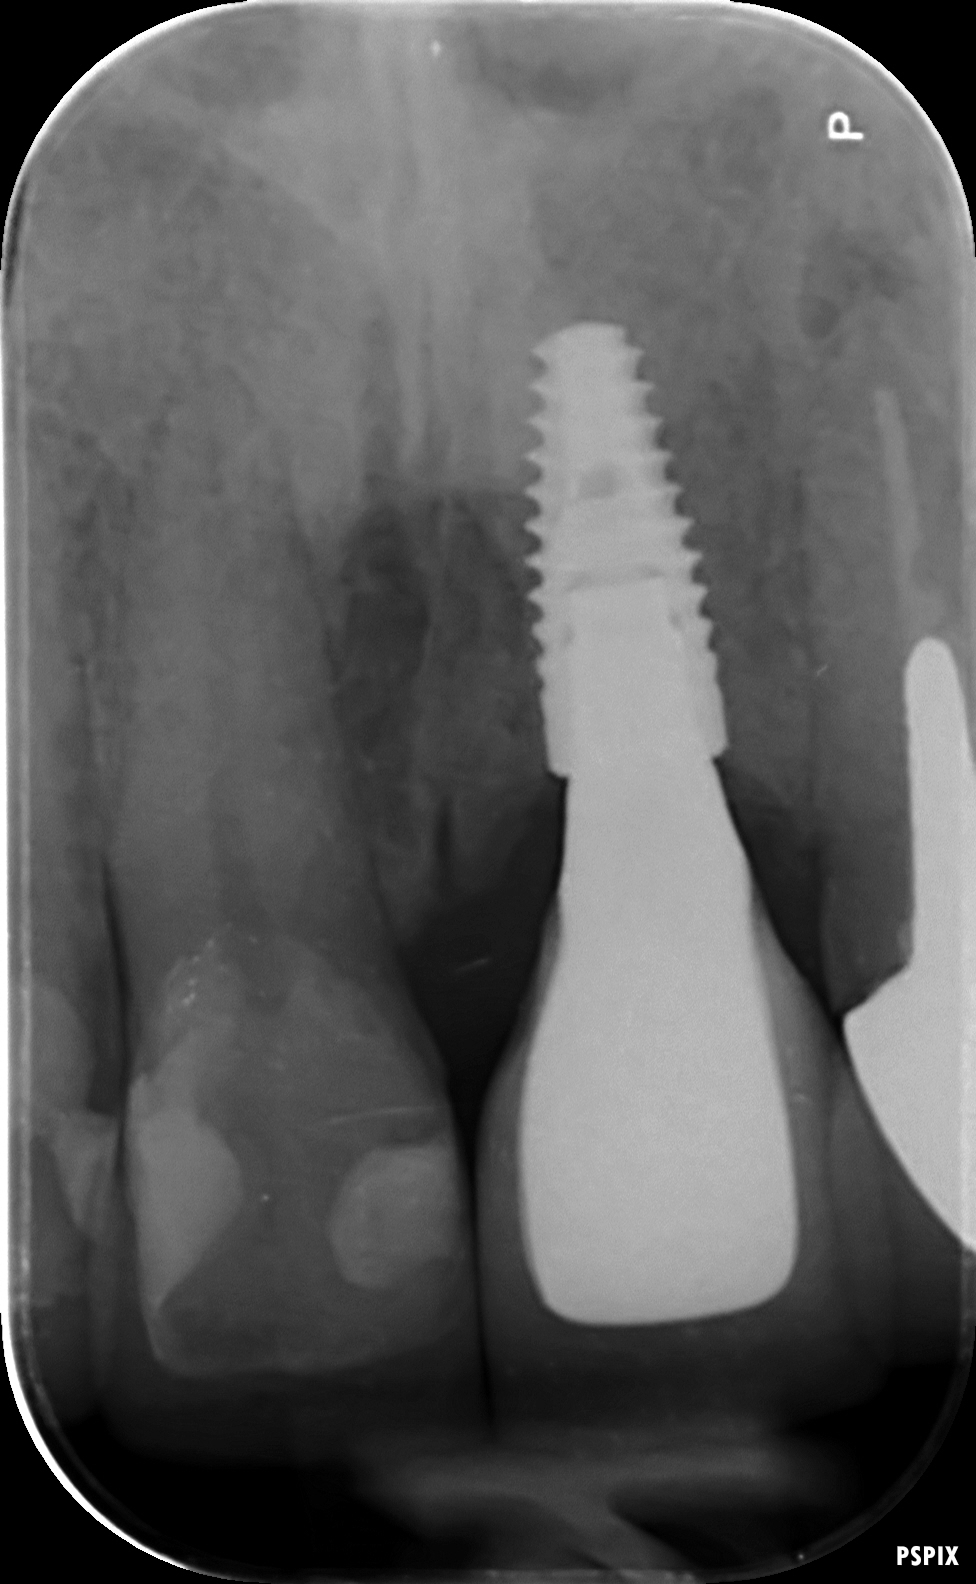

A dental implant is made from titanium and resembles a small screw. Once placed, the surface of the implant interacts with the surrounding bone to form a strong bond and a natural looking artificial tooth (the crown) can then be connected to the implant.

Treatment consists of three phases – planning, surgical, and restorative. The surgical phase consists of a minor procedure to place to implant and often requires the use of a small amount of bone grafting if there is insufficient natural bone. After the implant has integrated with the bone, the new artificial teeth will be designed and constructed to fit over the implants.